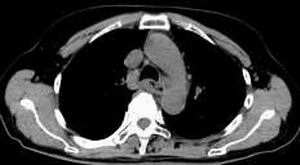

女,61岁,吞咽困难(包括开水)已久。

食道中上段癌并锁骨上窝淋巴结转移.

1、同意食道上段ca併淋巴结转移。

2、做食道呑钡就一目了然。

3、右侧甲状腺是否有问题?是否甲状腺ca转移食道上段。因为肿块顶部图像没有,请楼主展示,谢谢!

食道中上段中分化鳞癌伴锁骨上淋巴结转移

大家都很正确,谢谢!